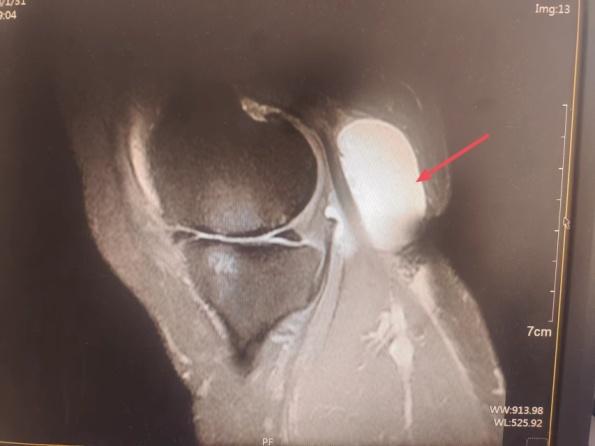

52岁的李女士最近发现左膝关节后方长了一个圆疙瘩,最初没在意,后来发现“疙瘩”越来越大,并且膝关节出现了发胀不适,来到寿光综合医院关节外科门诊就诊,常炳营主任检查后考虑为“左膝腘窝囊肿”,患者住院准备手术切除。

腘窝囊肿是一种常见的膝关节良性疾病,也称为Baker囊肿,成年人腘窝囊肿发病主要是由于膝关节腔内积液形成,压力增高,关节液经后关节囊的薄弱区(腓肠肌内侧头与半膜肌肌腱滑囊)膨出,形成囊肿,这种囊肿一般有一单向阀瓣与膝关节腔相通。